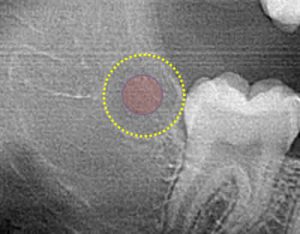

Zero3 technology accurately positions the center of the ablation in the center of the tooth bud.

An under-ablated tooth bud can result in a partial or deformed tooth formation.